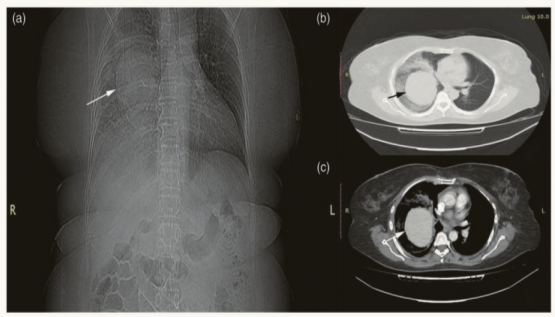

2025年4月26日患者外院胸部CT示:左侧胸腔积液伴左肺膨胀不全,左肺多发蜂窝状密度增高影,提示坏死性病灶可能,左肺上叶实性团块,占位性病变可能,右肺上叶小的厚壁空洞形成(图1)

1  患者外院胸部CT(2025-04-26)

中年男性,急性起病,咯血、胸痛、呼吸困难伴发热;血WBC、CRP、PCT显著升高;CT提示左肺多发蜂窝状密度增高影,伴左侧胸腔积液,右肺厚壁空洞;血胸,胸水分叶核为主;呼吸频率37次/min,PFR 134.7 mmHg;多肺叶浸润,尿素14.0 mmol/L(↑)。

患者咯血,左侧血胸,胸部CT提示左肺团块影,血细胞角蛋白19片段2.84 ng/ml(↑),鳞状上皮细胞癌抗原2.8 ng/ml(↑)。左肺占位性病变,有无肺部肿瘤可能性?回溯患者在我院2023年的胸部CT,未见结节和肿块(图2)。但经过2年时间,病变也可能出现进展。